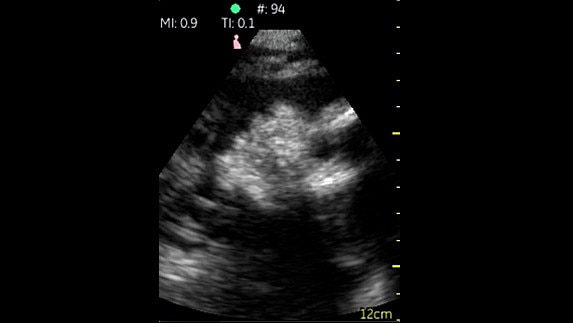

Phased Cardiac